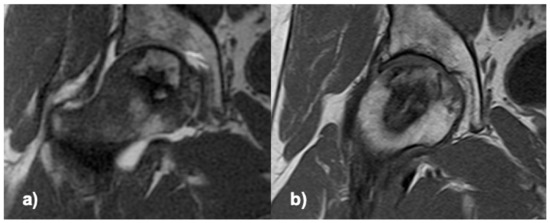

Clinical and radiological regeneration (Figure 2), with maintained head sphericity, was observed in 80% of the treated patients (16/20) after a one-year follow-up, 73% (16/22) on ITT (including 2 drop-out cases only evaluated at 3 months). Four cases progressed to the next stage of ON (4/20), and of these, 3 received THR. Generalized estimating equation analysis (model adjustment: Wald Chi-square = 177.35; p = 0.001) for pain higher than 30/100, age higher than 50, time since diagnosis higher than 3 months, positive alcohol consumption, and positive smoking habit, only showed a significant interaction of ON progression/THR with pain (OR = 3.8 [3.0–4.7]; p = 0.001).

Figure 2.

T1 MRI of the femoral head, coronal section through the ON area; (a) preoperative, (b) 6 months after delivering the cells.